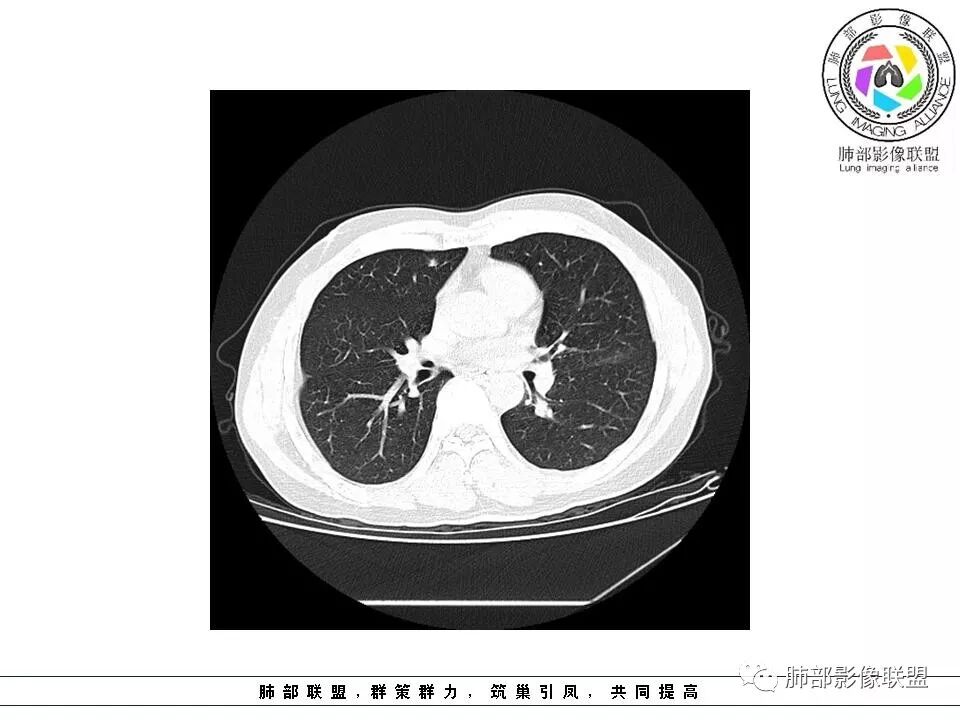

如果实性病变,边缘收缩,可以考虑炎性, 但是边缘有边界清楚GGO,一定要警惕恶性,还有粗短毛刺更要小心撇开其它,看到这个图,除非你怀疑假象,不然就是要考虑腺癌的可能

边界清楚GGO,短毛刺,这要小心瘢痕癌可以多为腺癌复查没变化,与血供有关,属于休眠期张国祯教授的理论:腺瘤样增生、原位癌都属于偏良性,就是没有侵袭性;以后发展——侵袭可以,不变可以,部分可能还会凋亡(比较少)

原位腺癌